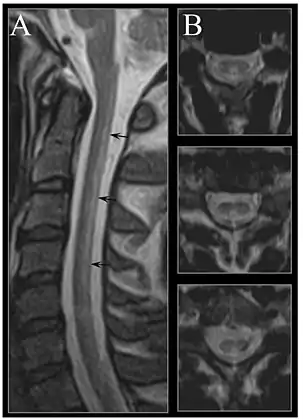

MRI of the brain may show periventricular white matter abnormalities. MRI of the spinal cord may show linear hyperintensity in the posterior portion of the cervical tract of the spinal cord, with selective involvement of the posterior columns.

MRI image of the cervical spinal cord in vitamin B12 deficiency showing subacute combined degeneration. (A) The midsagittal T2 weighted image shows linear hyperintensity in the posterior portion of the cervical tract of the spinal cord (black arrows). (B) Axial T2 weighted images reveal the selective involvement of the posterior columns.